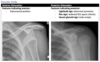

AC joint dislocation

Anterior vs posterior shoulder dislocation on XR

Anterior shoulder dislocation

Posterior shoulder dislocation